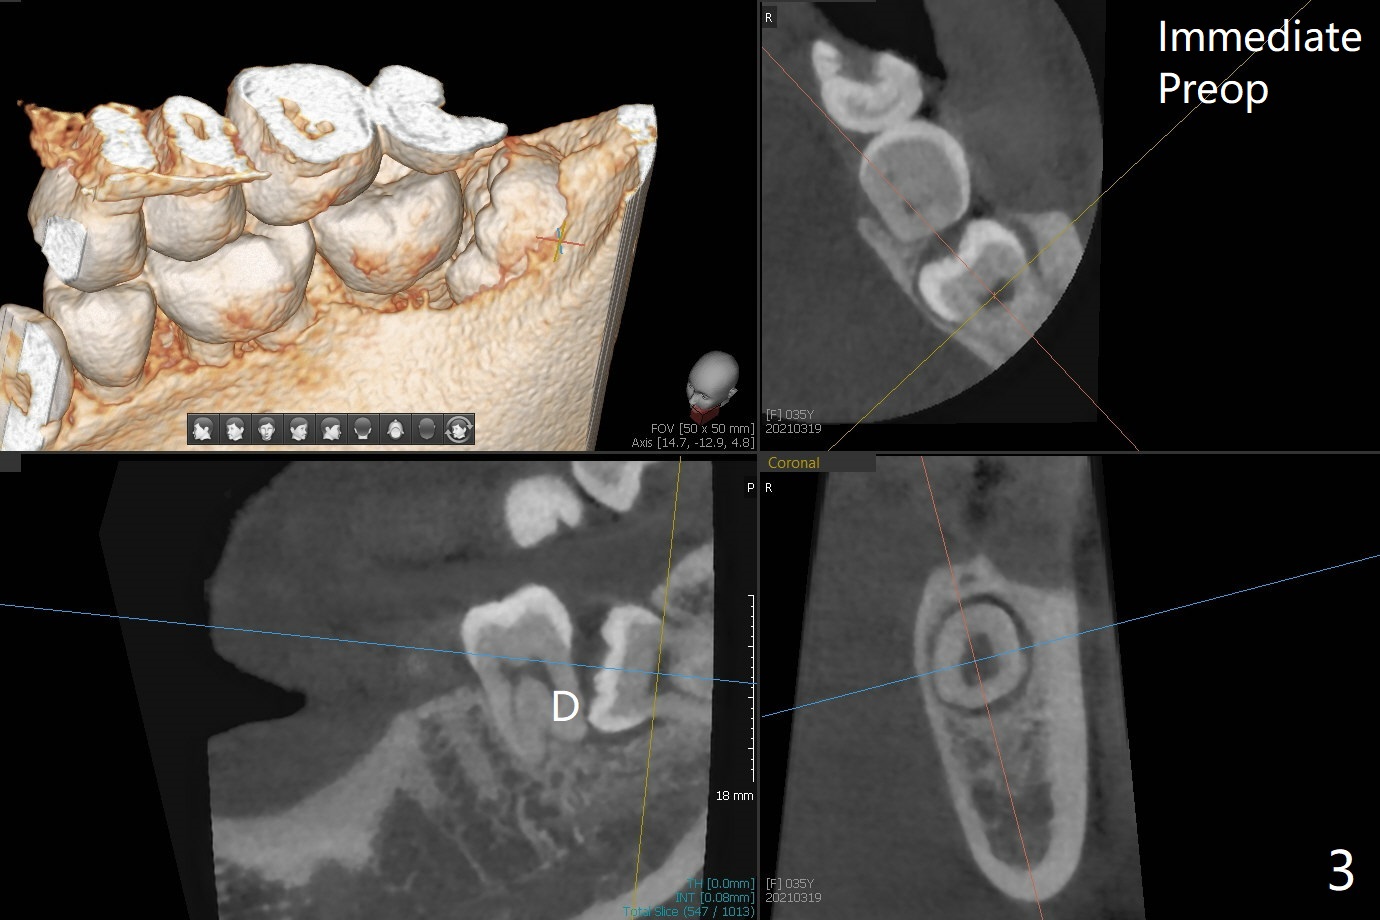

A 35-year-old timid woman finally decides to have 4 of the 3rd molars extracted (Fig.1). The apices of #17 overlaps with the Inferior Alveolar Canal (*). Small field CT shows that #17 is buccal to #18 (Fig.2), causing distal root exposure (Fig.3 D). In fact the buccal overlap seems to be more severe clinically (Fig.4) than what X-ray indicate (Fig.1,3). Therefore bone graft seems to be able to be packed mesially (Fig.5: G). In fact the left Inferior Alveolar Canal is exposed after extraction, collagen plug (P) is placed distal without use of curette around the exposed canal.